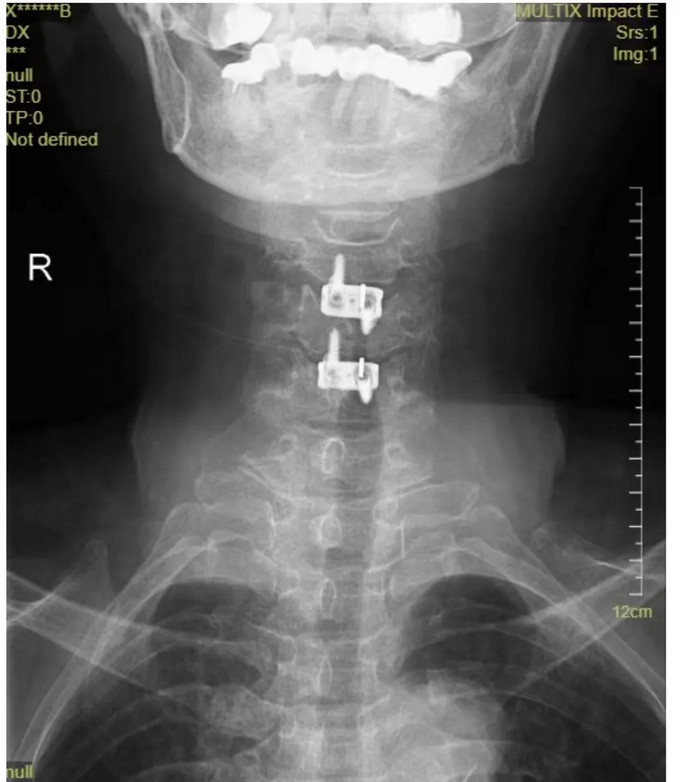

頸椎正位DR

頸椎CT橫斷位 可以看到突出的骨贅已被切除